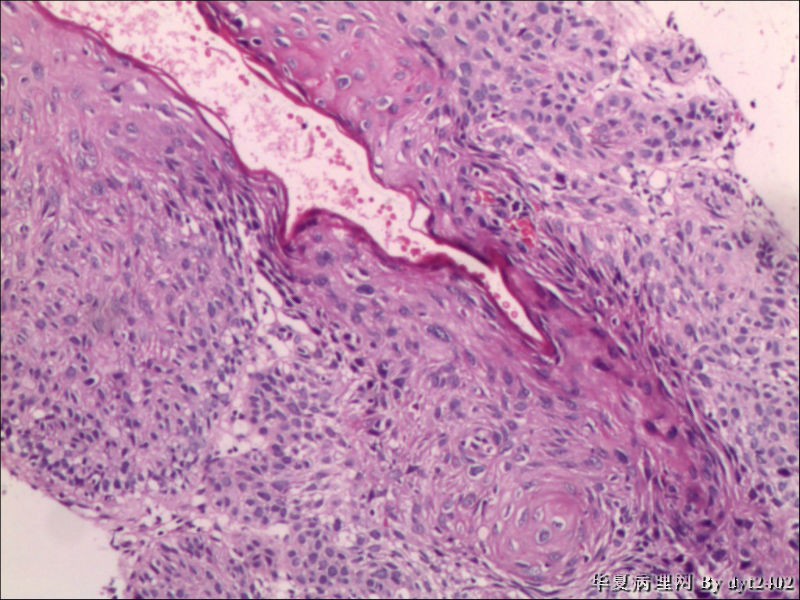

• 宫颈活检 其中一点较迷糊图2

图2

四点中三点是CIN iii,另一点怀疑有更重病变

这个病人是44岁,去年11月底阴道脱落细胞、TCT均见细胞异常,建议活检,病人犹豫,接着单位组织到外院体检时做阴道镜正常,后霉菌感染,此时宫颈未涂醋肉眼看还光滑,直至今年3月来做活检,事前做白带检查又见异常细胞,宫颈未涂醋见后上唇白上皮,涂醋酸后上下唇都有厚白上皮,镶嵌,夹活时上皮剥脱,未能夹到间质,阴道镜医生说至少有CIN III 到原位癌了。。镜下其中3点CIN III无疑,唯有9点处如6、7、11、14等所示结构,但我未见间质浸润,不能说是浸润癌,不知道有没基底细胞样鳞癌的可能,我发了个原位癌不除外深部有更重病变,。